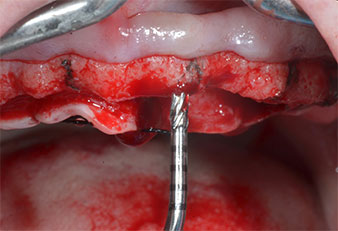

Ултразву��ов пилотен накрайник за Piezomed

Фиг. 3 Препарацията с ултразвуков пилотен накрайник I1 се извършва с движение нагоре-надолу, успоредно с дългата ос на работната част.